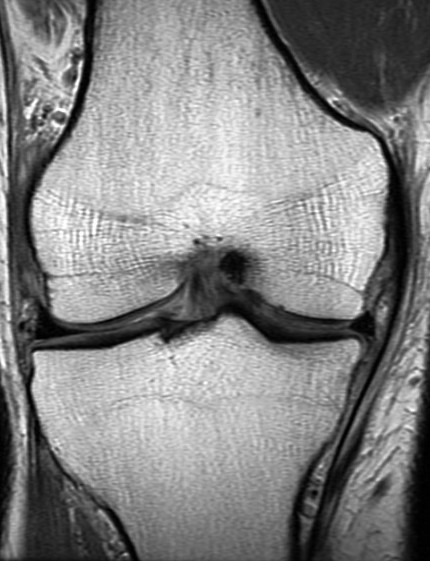

44 y/o male recreational runner. 2 week history of medial pain. r/o mmt.

Bone marrow edema is the radiologists friend. The posterior horn tear is easy to see. The displaced meniscus flap into the coronary recess adjacent to the body of the meniscus isnt so easy to see. The presence of bone marrow edema should alert us to the possibility of adjacent pathology leading to the reactive changes in the bone.

Unstable displaced medial meniscus tear( RID2772 ) with reactive tibial edema